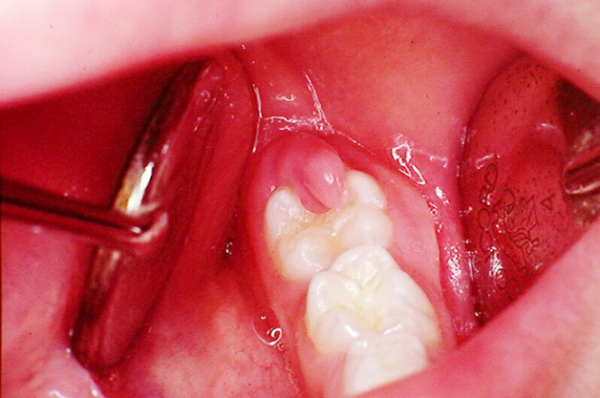

Răng khôn bị lợi trùm tức là chiếc răng khôn chỉ mọc được một phần ra bên ngoài, 1 phần của nó bị che lấp bởi lợi. Trường hợp lợi trùm còn thể hiện túi lợi quanh răng. Khi nhìn bằng mắt thường bạn thấy lợi không che phủ lên bề mặt răng nhưng tại một số điểm lợi quá phát làm xuất hiện túi sâu. Những túi này thường đọng thức ăn, thức ăn rơi xuống đáy túi khiến bạn không thể sử dụng những biện pháp vệ sinh thường quy để lấy ra được.

Đây là biểu hiện thường gặp phải khi bạn gặp các vấn đề về răng miệng. Phần lợi trùm trên chiếc răng khôn đang mọc bị tấy đỏ, sưng phồng, khi ấn vào sẽ cảm thấy đau đớn, thậm chí có thể thấy chảy nước và mủ.